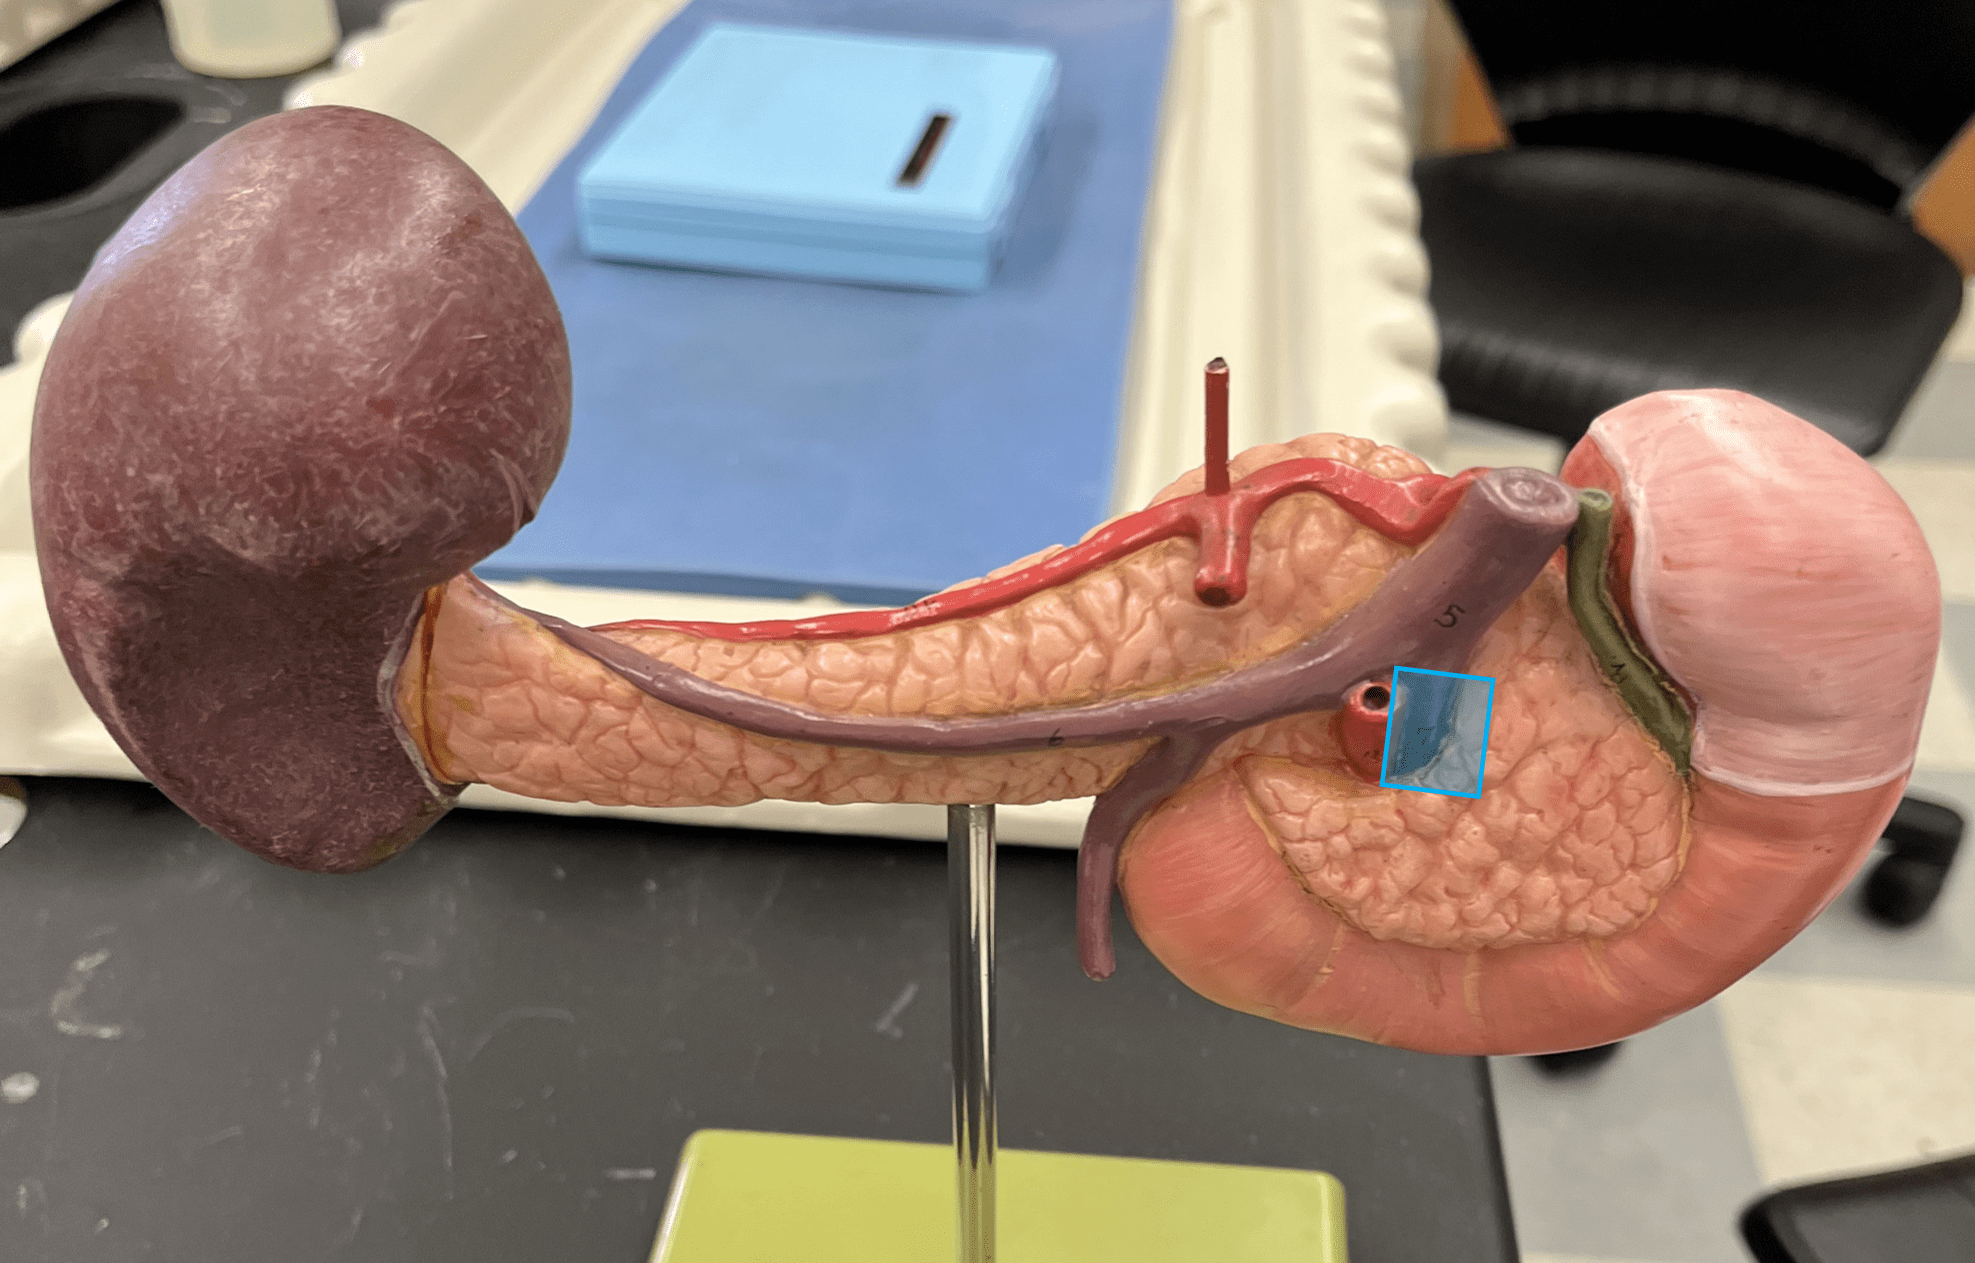

tunica externa

• The outermost layer of an artery wall.

• Composed of loose connective tissue and collagen fibers.

• Also known as the tunica adventitia.

• Composed of loose connective tissue and collagen fibers.

• The smooth muscle allows for vasoconstriction and vasodilation.

9

New cards

internal elastic membrane

• A thin layer of elastic connective tissue.